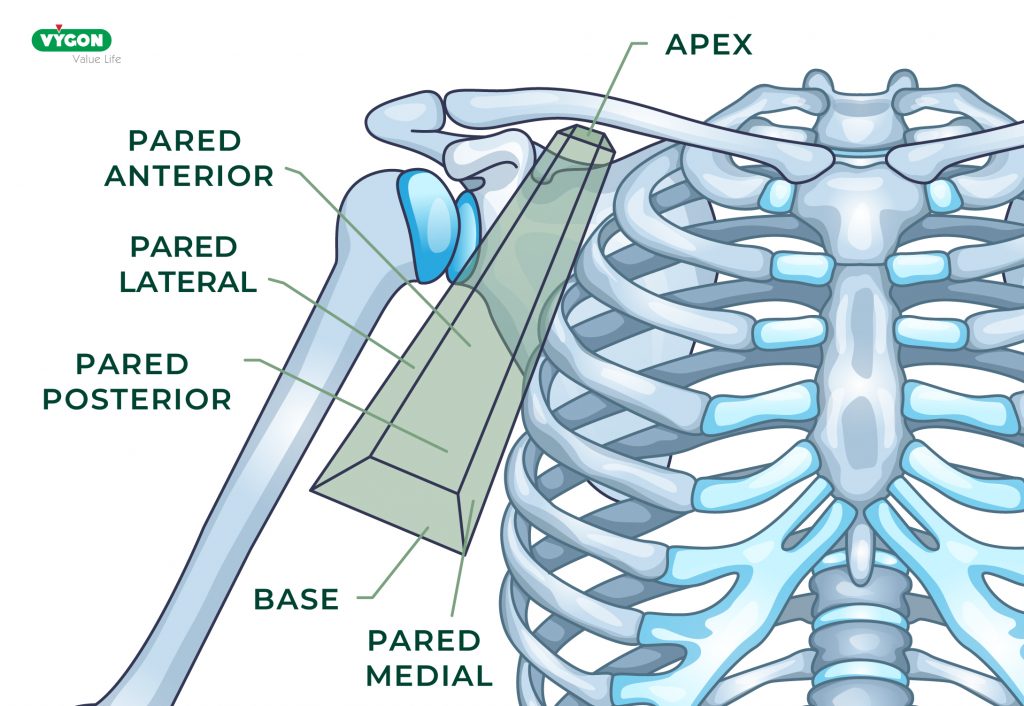

El espacio axilar

Ente el punto medio de la clavícula y el húmero proximal se localiza el espacio axilar anatómico, el cual tiene forma de pirámide truncada.

La base del espacio axilar está formada por la fascia axilar (que incluye al ligamento suspensorio de la axila) y la piel que la cubre en el extremo más proximal del brazo en su unión con el tronco.

La pared anterior del espacio axilar es importante para comprender las relaciones anatómicas de los abordajes infraclaviculares y está formada por los músculos pectorales mayor y menor.